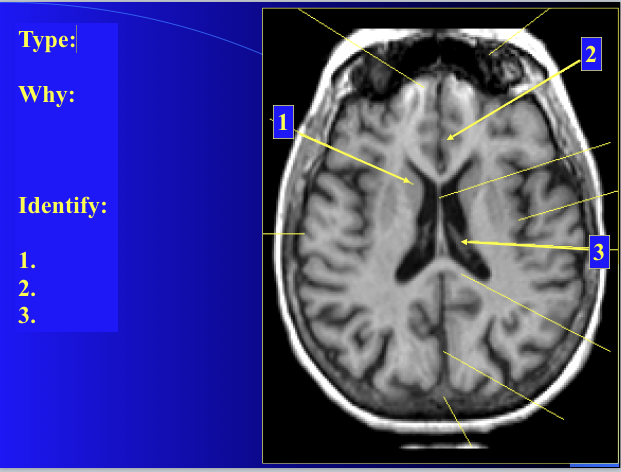

is this T1 or T2?

T 1

what type of image is this?

how do you know?

what is the enhancement?

T2

CSF is very bright

none